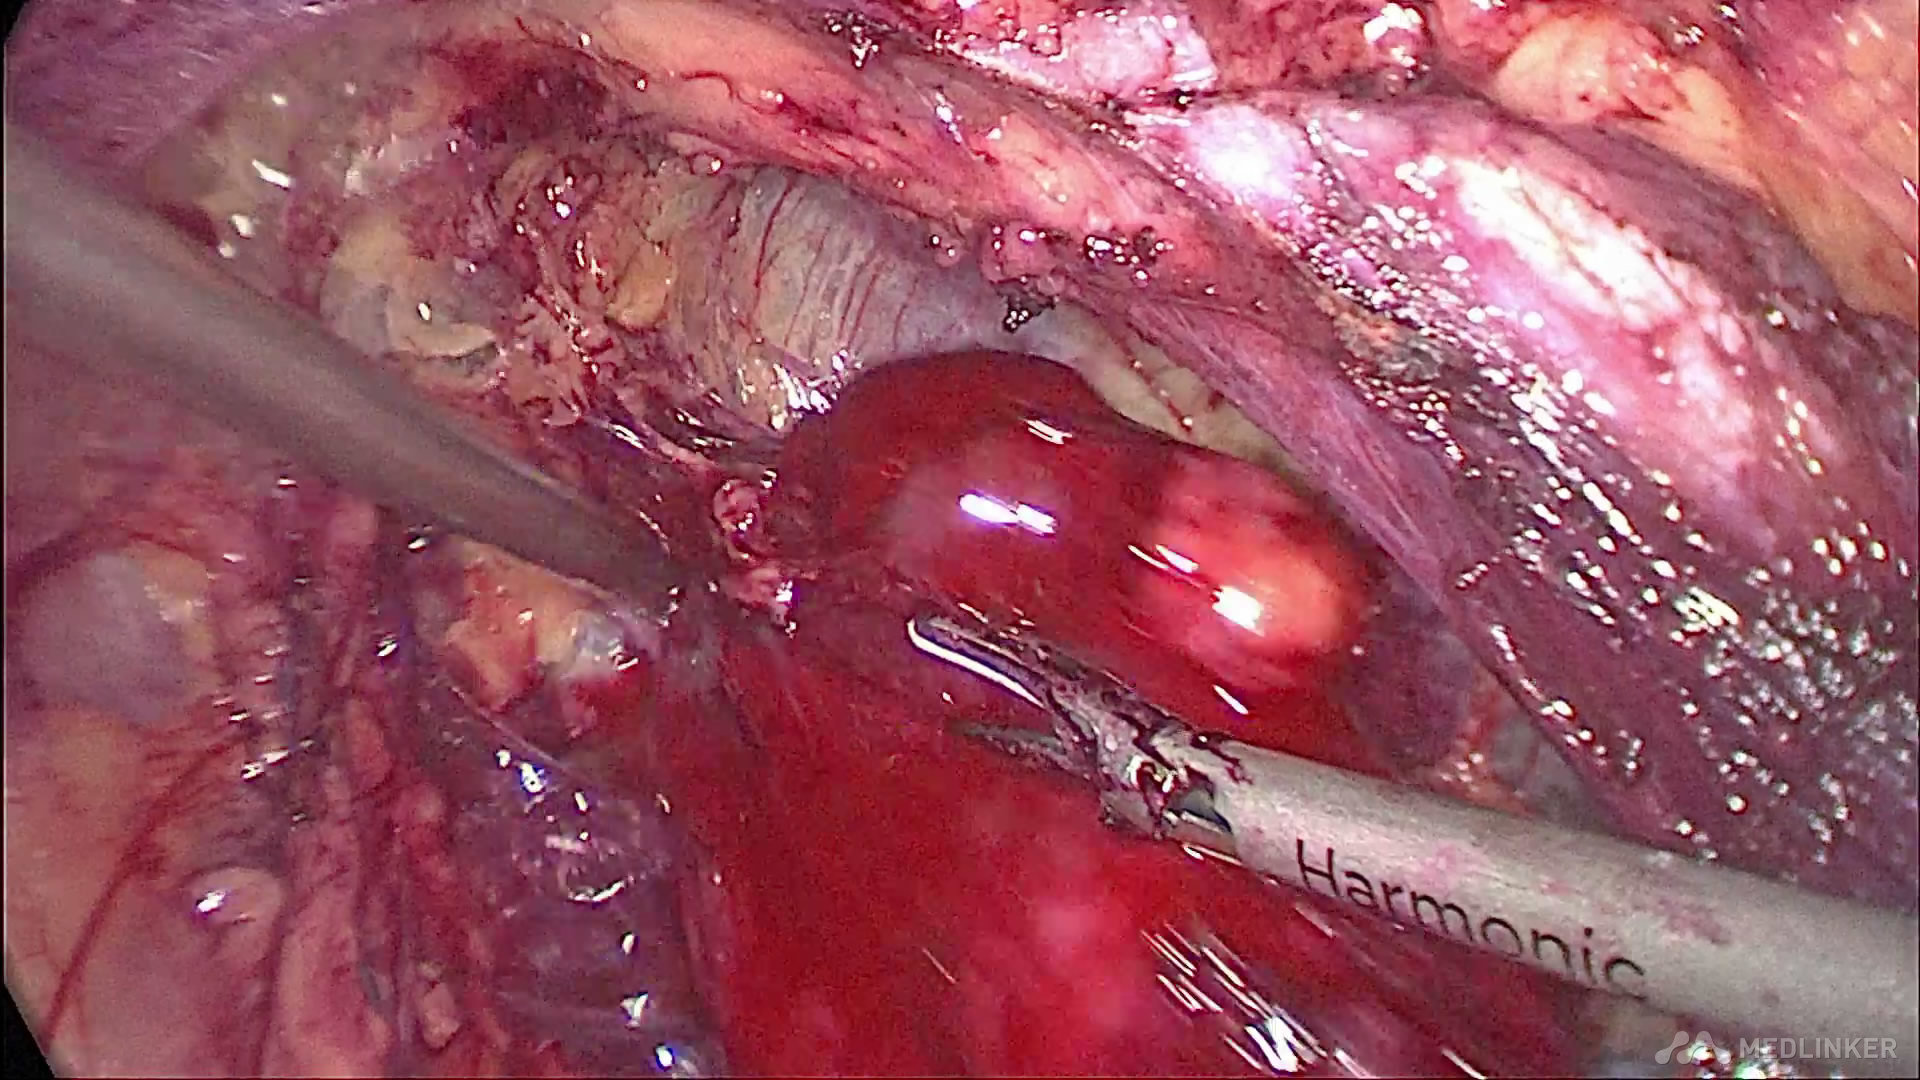

沿下腔静脉寻及右肾蒂,充分游离右肾动脉

阻断右肾动脉及分支,防止切除肿瘤时大出血的发生

沿肿瘤包膜切除右肾肿瘤,在控制右肾动脉的情况下,创面出血不多,以渗血为主

完整切除肿瘤,发现肿瘤脂肪成分较多,快速病理提示符合右肾错构瘤改变